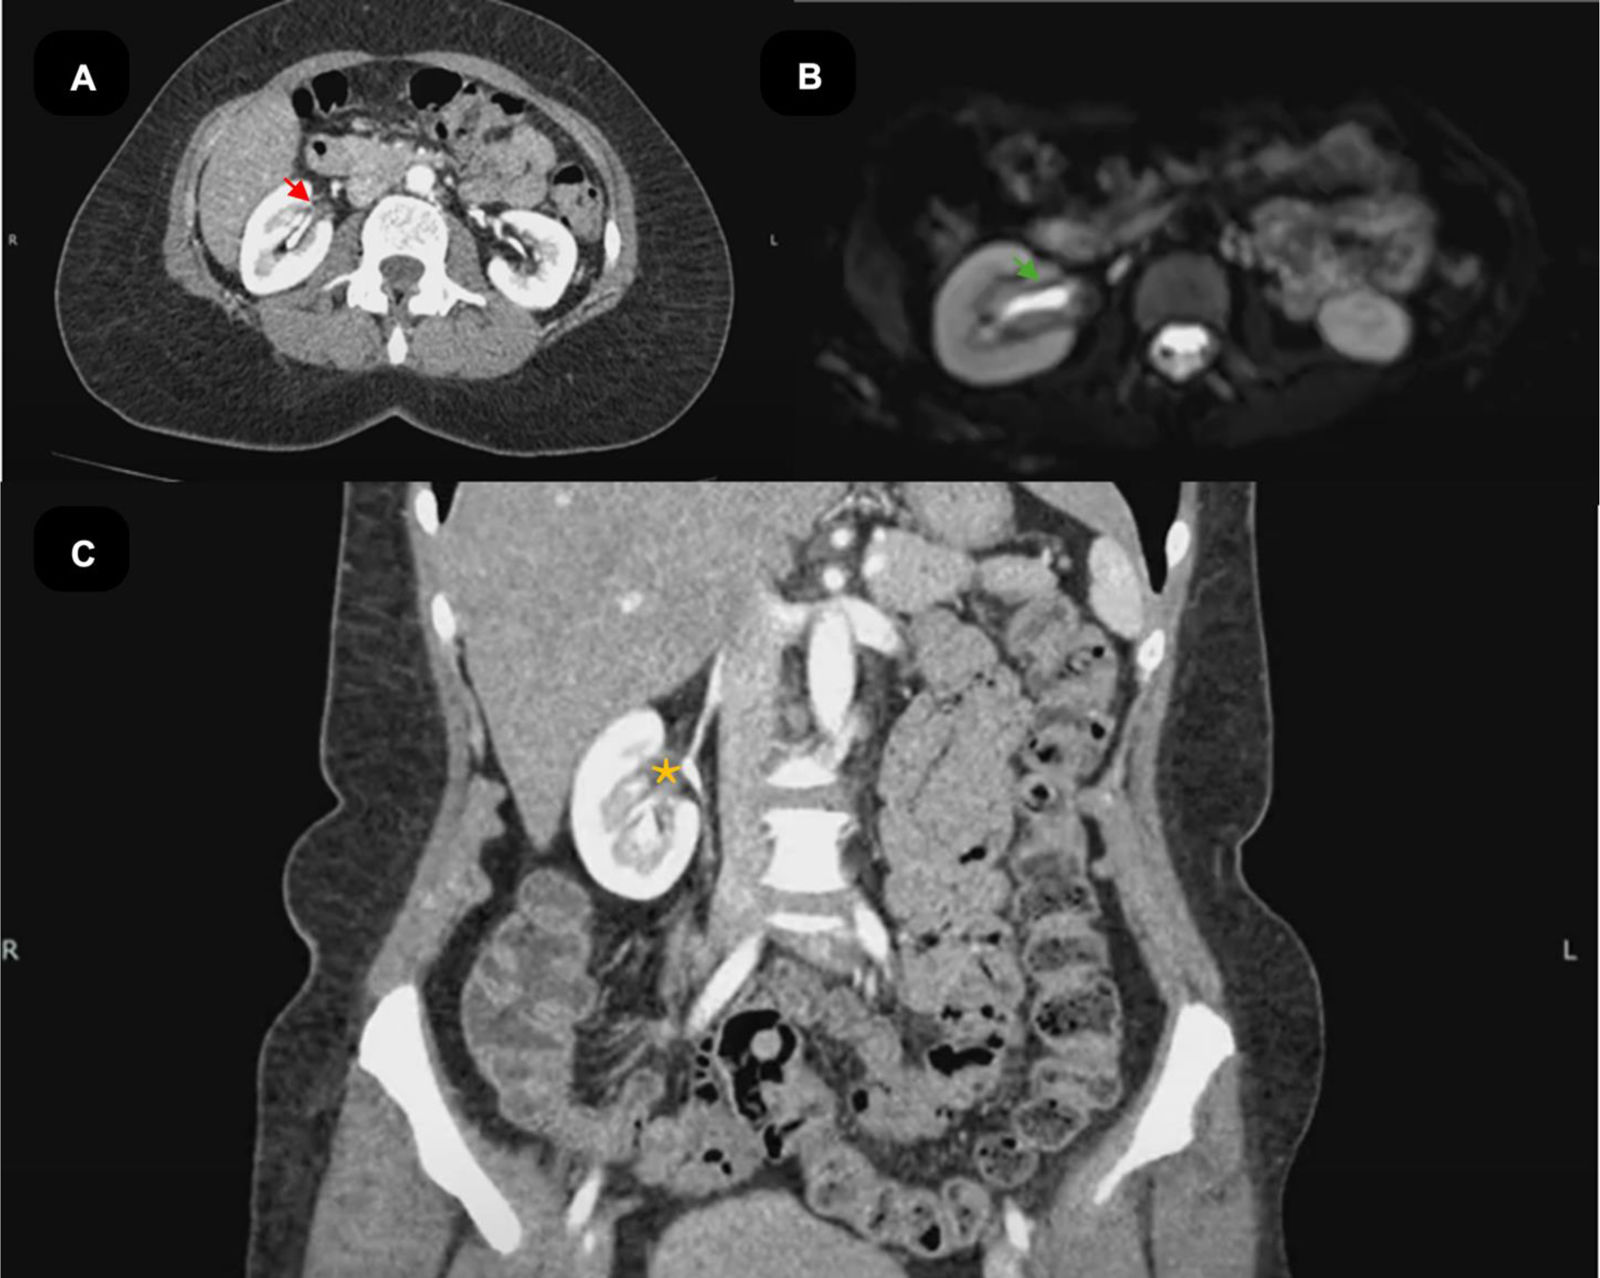

During the course of the disease, the patient developed abdominal pain. A contrast-enhanced abdominal CT scan revealed irregular thickening of the renal pelvis walls and the proximal right ureter. Serial urinary cytology ruled out associated neoplastic pathology (Fig. 4). Given the extensive organ involvement, the risk of renal injury, and the potential for organ dysfunction, treatment with Rituximab 1g dose was initiated on days 0 and 15 [9].

Abdominal magnetic resonance imaging (MRI) and computed tomography (CT). (A) Contrast-enhanced computed tomography (CT), axial view, demonstrating thickening of the right ureteral wall with enhancement (red arrow). (B) Magnetic resonance imaging (MRI), diffusion-weighted imaging (DWI) sequence, axial view, showing signal restriction consistent with active inflammation and tissue infiltration of the right ureter (green arrow). (C) Contrast-enhanced computed tomography (CT), coronal view, revealing mild hydronephrosis due to dilation of the right renal pelvis (orange asterisk).